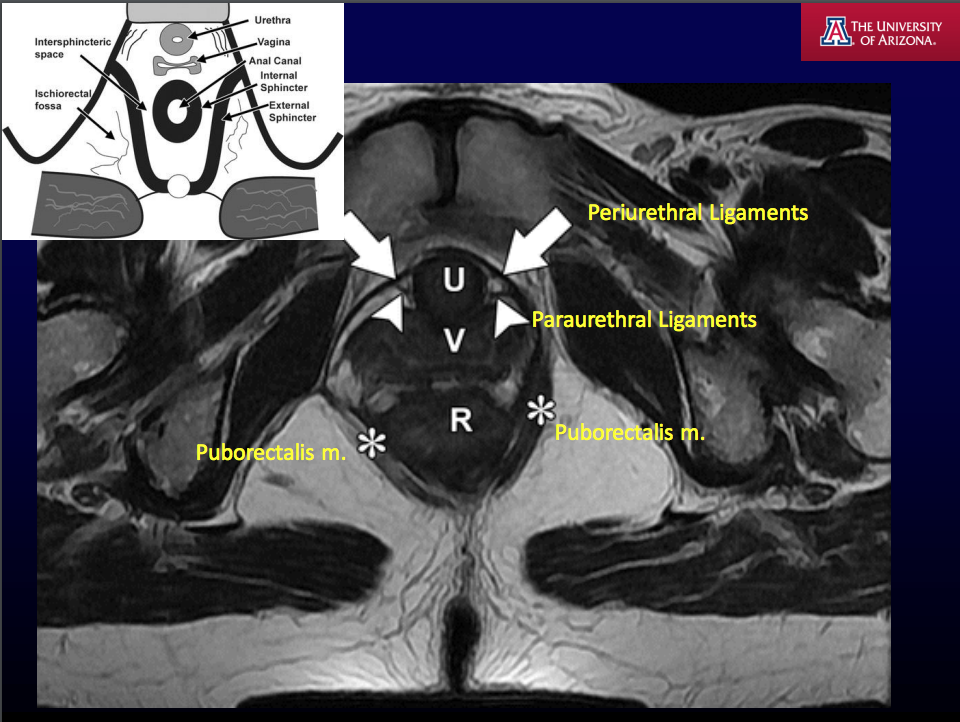

MRI T2WI fat is [] and fluid is [].

MRI T2WI fat is bright and fluid is bright.